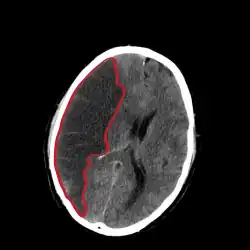

Als Mediainfarkt wird eine besonders lokalisierte Form des ischämischen Schlaganfalls (Hirninfarkt) bezeichnet. Der Ausdruck bezieht sich auf einen Verschluss eines der Hauptgefäße im Gehirn, der Arteria cerebri media („mittlere Gehirnarterie“). Etwa 50 % der Hirninfarkte liegen im Versorgungsgebiet der Arteria cerebri media.[1]

Es wird grob zwischen komplettem Mediainfarkt und Mediateilinfarkt unterschieden. Eine Sonderform ist der maligne Mediainfarkt, der aus großen Mediainfarkten entstehen kann. Er ist gekennzeichnet durch eine lebensgefährliche Hirndrucksteigerung, die durch das 2–5 Tage nach Infarktereignis entstehende Infarktödem verursacht wird.

Nach Ausschluss einer Blutung mittels Computertomographie und Ausschluss anderer Kontraindikationen wird eine zügige Lysetherapie angestrebt, wenn das Zeitintervall zwischen Symptombeginn und Therapiebeginn nicht länger als 4,5 Stunden ist. Prinzipiell sollte der Patient einer möglichst schnellen Behandlung in einem Krankenhaus mit Stroke Unit zugeführt werden. Es gibt darüber hinaus die Möglichkeit, einen Hirninfarkt mittels eines interventionellen Verfahrens zu therapieren.